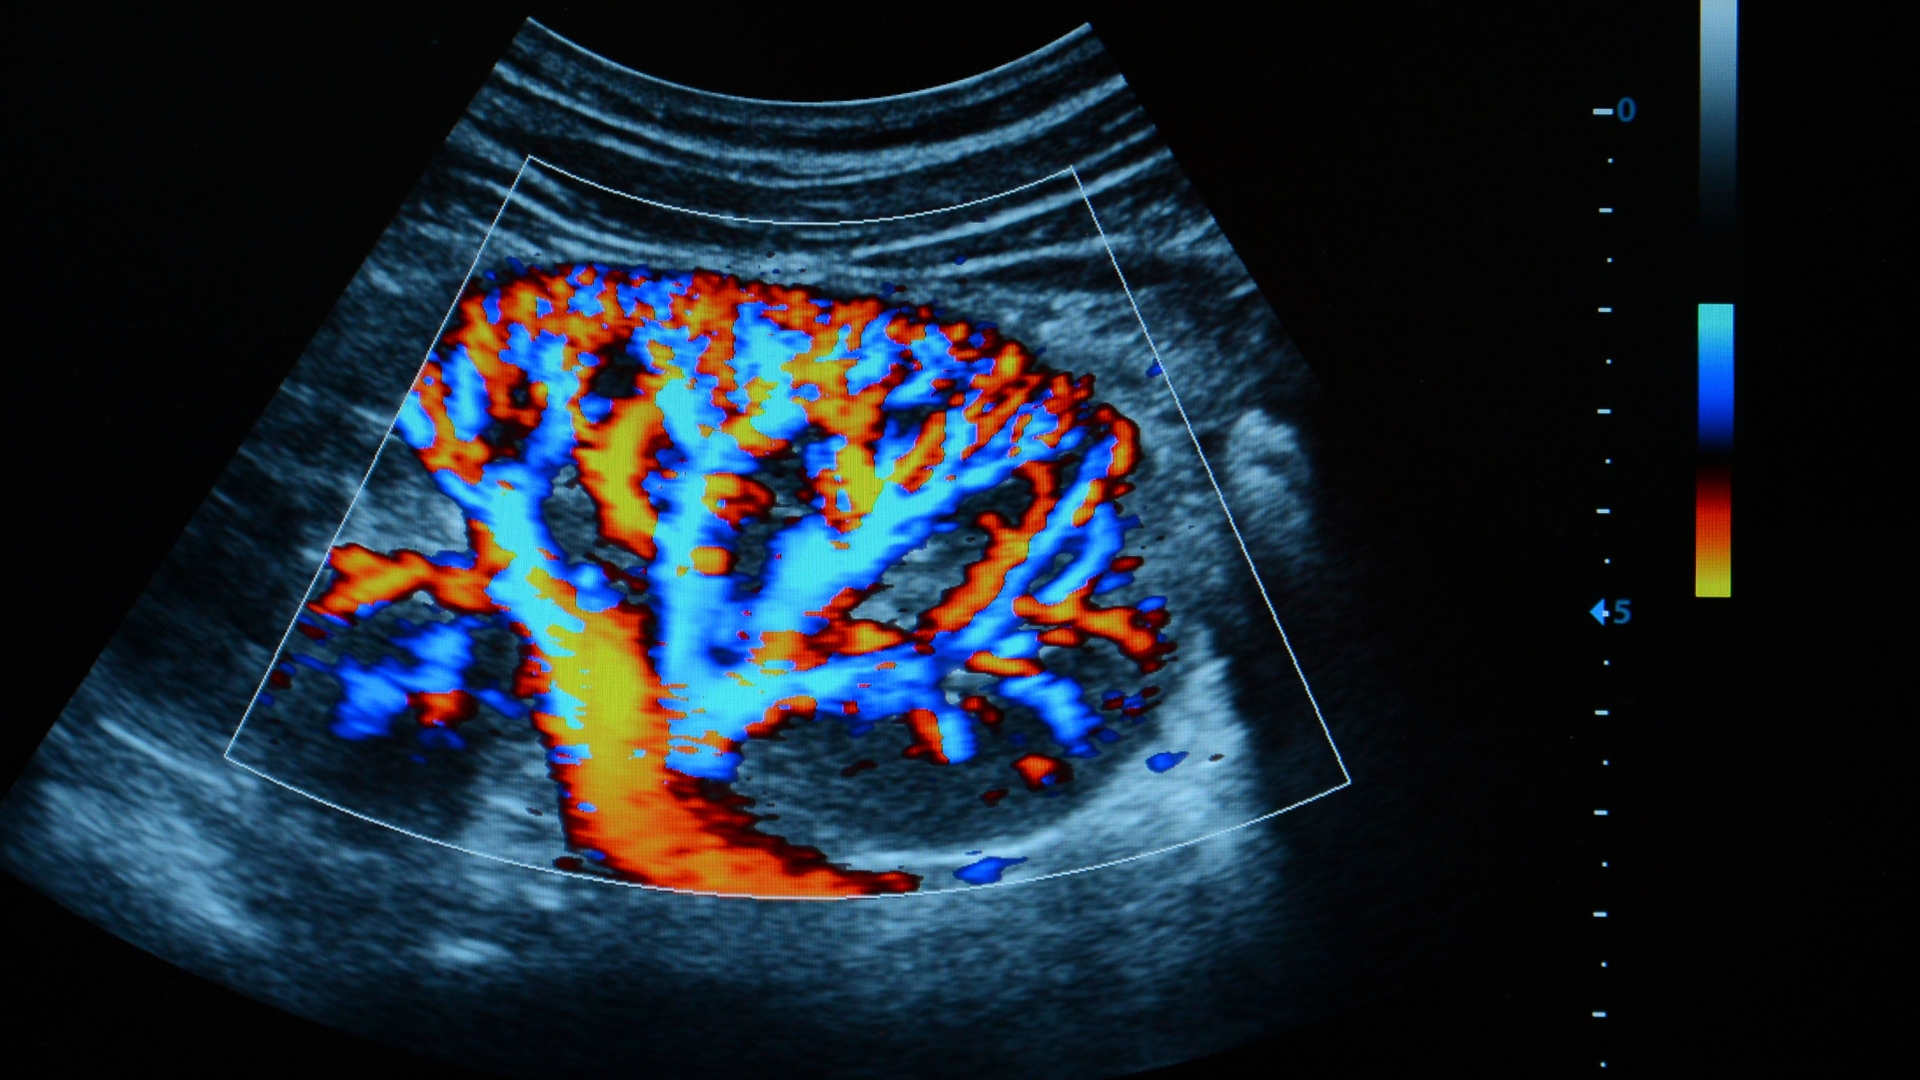

Kỹ thuật Doppler là phần quan trọng của siêu âm mạch. Doppler cho phép ghi lại tốc độ và hướng dòng máu dựa trên sự thay đổi tần số của sóng phản hồi. Điều này giúp phát hiện tình trạng hẹp, tắc, xoáy dòng hoặc suy giảm tưới máu. Hình ảnh Doppler màu hỗ trợ mô phỏng dòng chảy trực quan, còn Doppler phổ cung cấp thông tin dạng sóng giúp đánh giá huyết động chi tiết hơn.

Suy tĩnh mạch mạn tính: Suy van tĩnh mạch khiến máu ứ đọng ở chi dưới, gây giãn tĩnh mạch, phù chân hoặc loét da. Doppler màu giúp đánh giá dòng chảy ngược và xác định van bị suy.